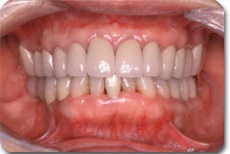

かみ合わせの改善を含めた総合的な治療により、このように崩壊したお口の中でも しっかり噛めて、美しい状態に治すことができます。この後は、定期的メインテナンスをお受けいただき、良い状態を守って行ければ長い期間、快適な食生活が営めるでしょう。どんな状態でも希望を持って、ご相談いただければ幸いです。

かみ合わせ治療によりここまで治すことができます